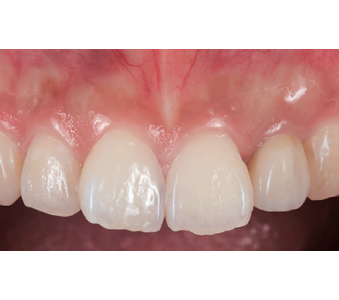

결과로 증명합니다.

국제모아치과의

실제 임상 증례